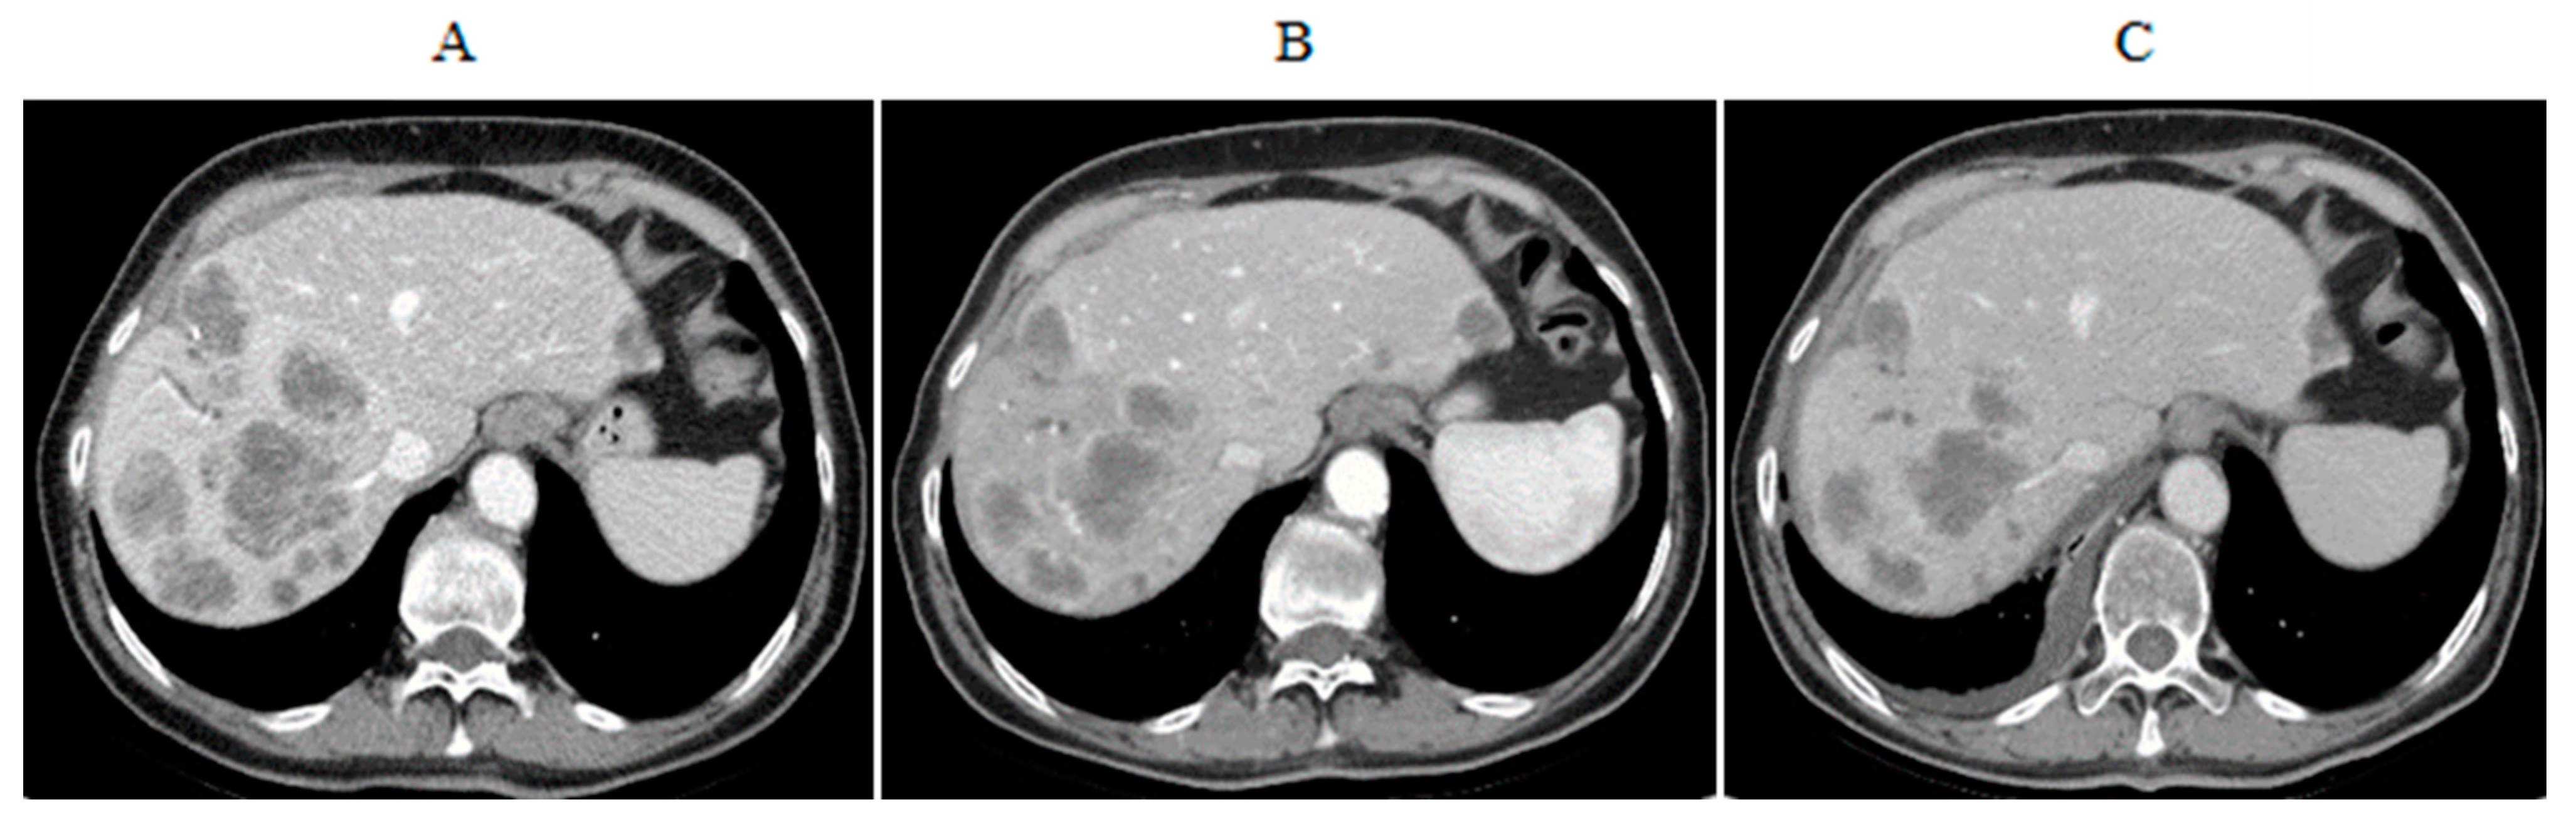

- Marquardt, S.; Kirstein, M.M.; Bruning, R. Percutaneous hepatic perfusion (chemosaturation) with melphalan in patients with intrahepatic cholangiocarcinoma: European multicentre study on safety, short-term effects and survival. Eur. Radiol. 2019, 29, 1882–1892. [Google Scholar] [CrossRef] [PubMed]